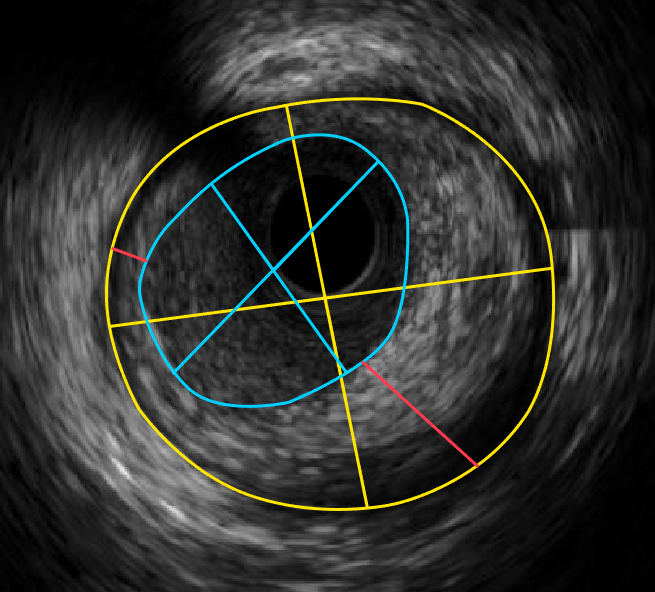

血管内超声机器 IVUS下显示的正常血管内部形态

通过血管内超声(IVUS)测量可以得到

黄色外弹力膜面积及其最大/最小直径

蓝色有效管腔面积及其最大/最小直径

红色最大/最小斑块厚度并可进一步计算出斑块面积和厚度以及偏心指数等